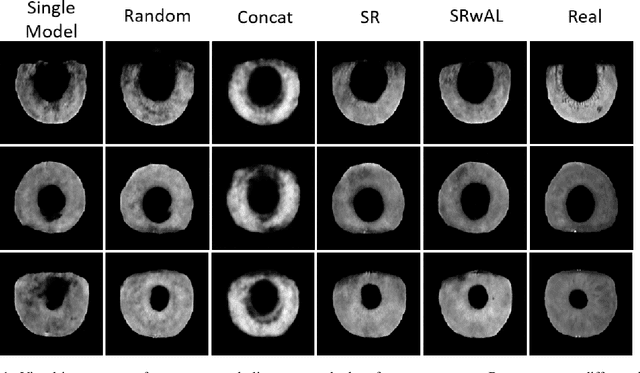

Authentication systems are vulnerable to model inversion attacks where an adversary is able to approximate the inverse of a target machine learning model. Biometric models are a prime candidate for this type of attack. This is because inverting a biometric model allows the attacker to produce a realistic biometric input to spoof biometric authentication systems. One of the main constraints in conducting a successful model inversion attack is the amount of training data required. In this work, we focus on iris and facial biometric systems and propose a new technique that drastically reduces the amount of training data necessary. By leveraging the output of multiple models, we are able to conduct model inversion attacks with 1/10th the training set size of Ahmad and Fuller (IJCB 2020) for iris data and 1/1000th the training set size of Mai et al. (Pattern Analysis and Machine Intelligence 2019) for facial data. We denote our new attack technique as structured random with alignment loss. Our attacks are black-box, requiring no knowledge of the weights of the target neural network, only the dimension, and values of the output vector. To show the versatility of the alignment loss, we apply our attack framework to the task of membership inference (Shokri et al., IEEE S&P 2017) on biometric data. For the iris, membership inference attack against classification networks improves from 52% to 62% accuracy.